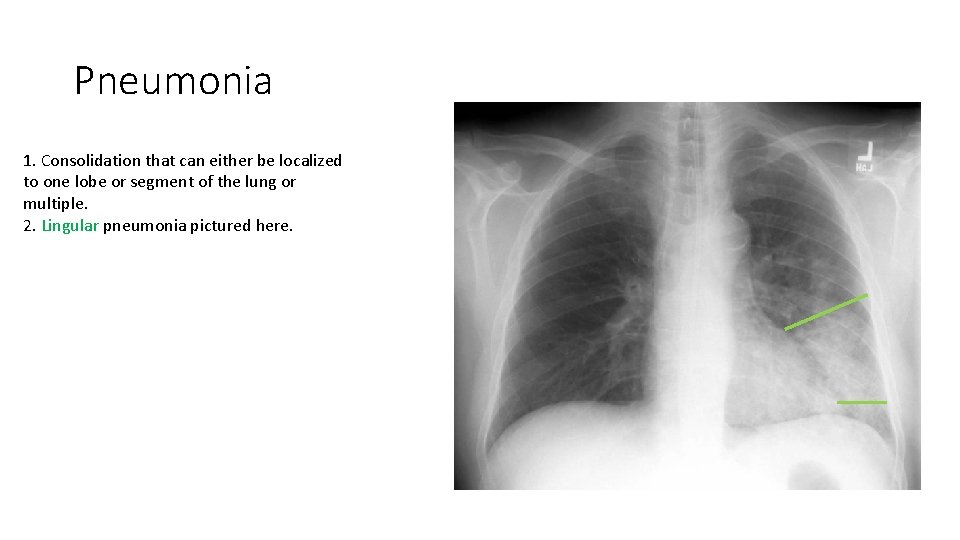

Pneumonia 1. Consolidation that can either be localized to one lobe or segment of the lung or multiple. 2. Lingular pneumonia pictured here.